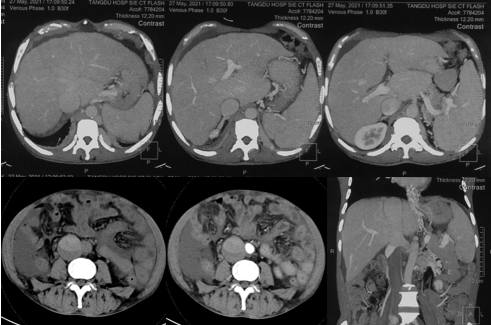

6月20日,患者及家屬懷揣著忐忑的心情來到西安國際醫(yī)學(xué)中心醫(yī)院找到韓國宏教授,韓教授詢問病情后閱患者外院CT片,明確診斷布加綜合征,同時發(fā)現(xiàn)了一個新的問題,在詢問病史時了解到患者近一周雙下肢乏力伴腫脹明顯加重,遂立即安排了急診CT,證實下腔靜脈內(nèi)急性血栓形成!

6月22日,在韓國宏教授的帶領(lǐng)下,患者于消化介入診療中心行下腔靜脈開通術(shù)。術(shù)中可見:下腔靜脈全段擴張,膜性閉塞,腎靜脈平面以下可見血栓形成并伴有粗大的側(cè)枝靜脈,遂對狹窄段球囊擴張并植入支架,術(shù)后下腔靜脈血流通暢,側(cè)枝消失。術(shù)后第2天,患者腹壁靜脈曲張幾乎消失不見,走路也輕快了許多。明明只是薄薄的一層膜,為什么開通起來這么難?韓教授指出,盡管布加綜合征介入開通技術(shù)已使創(chuàng)傷降到了最低,但受到患者個體差異及醫(yī)療水平參差不齊的限制,仍有可能出現(xiàn)嚴重的并發(fā)癥,主要包括:心包積血、縱隔血腫、心包填塞甚至下腔靜脈撕裂引起的大出血等。而其發(fā)生率與術(shù)者的操作熟練程度及經(jīng)驗有很大的關(guān)系。